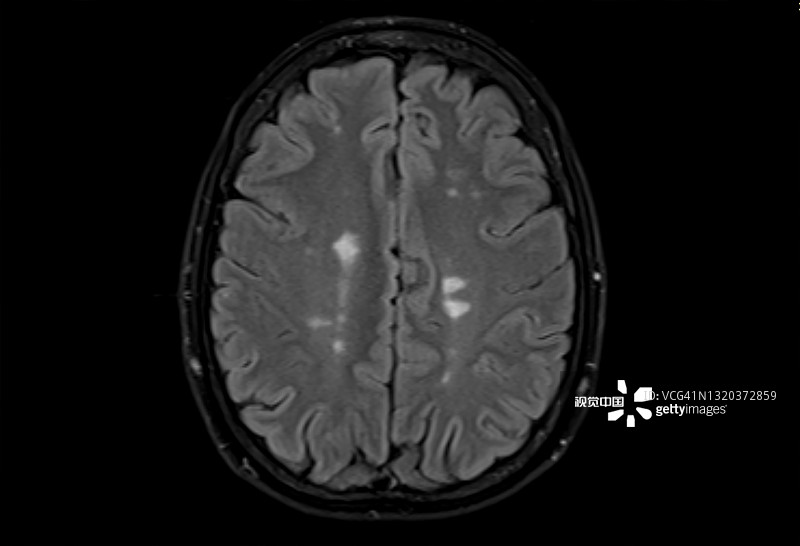

多發(fā)性硬化癥 (MS):MS是一種中樞神經(jīng)系統(tǒng) (CNS) 的慢性自身免疫和炎癥性疾病。MS與免疫系統(tǒng)介導(dǎo)的自身反應(yīng)性T細(xì)胞和B細(xì)胞對神經(jīng)元髓鞘的攻擊有關(guān),導(dǎo)致脫髓鞘并最終導(dǎo)致神經(jīng)元丟失。由于中樞神經(jīng)系統(tǒng)中神經(jīng)變性和斑塊的形成,MS患者會根據(jù)斑塊的位置經(jīng)歷特定的神經(jīng)功能障礙。例如,視神經(jīng)中的斑塊會導(dǎo)致視力喪失。